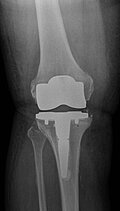

Kurze Vorgeschichte: Herr S, ein 67-jähriger Patient, erhielt 2011 (Abbildung 1) bei ausgeprägter Gonarthrose eine primäre KTEP rechtsseitig. Im weiteren Verlauf zog er sich 2017 eine periprothetische Tibiafraktur zu, die mit einem Knieendoprothesenwechsel auf ein achsgeführtes Implantat (Abbildung 2) und Schaftverlängerung der Tibia im September 2017 ex domo therapiert wurde. Im Verlauf zeigten sich eine anhaltende Sekretion und eine partielle Nekrose am unteren Wundpol.

Eine Röntgendiagnostik des rechten Kniegelenkes in 2 Ebenen wurde eingeleitet. Hierbei zeigte sich eine stabil einsitzende Revisionsprothese ohne aktuelle Lockerungszeichen.